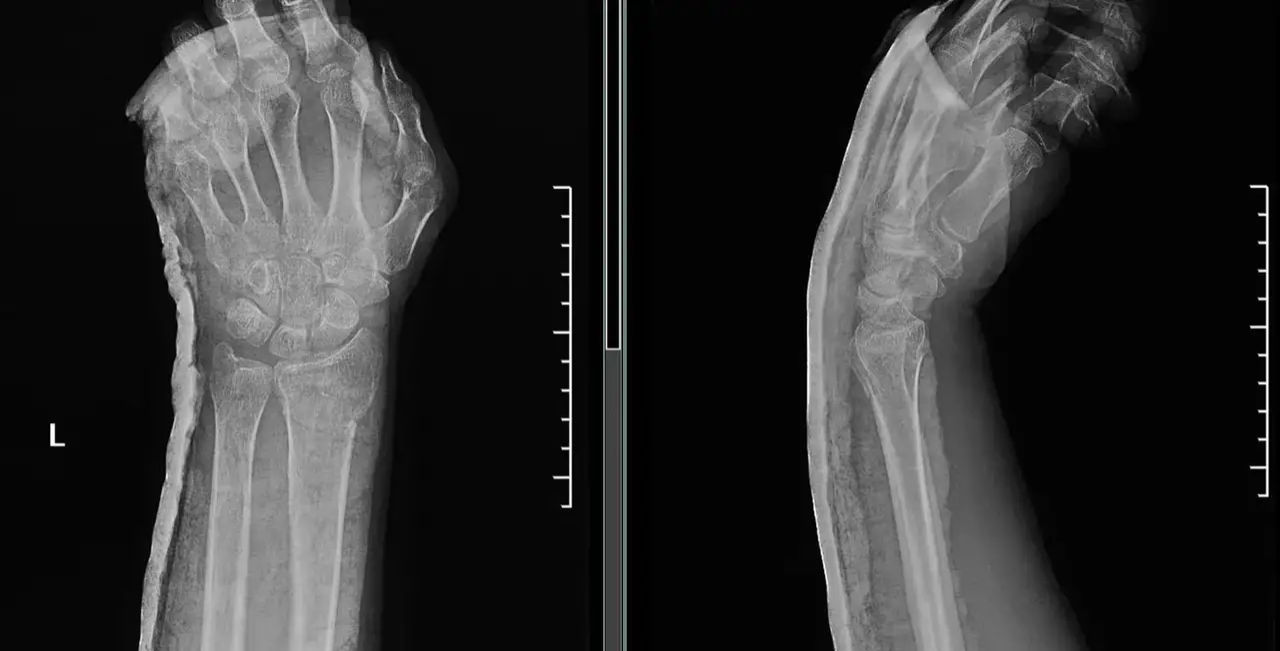

临床工作中,对于骨折的治疗,许多时候我们常常采取保守治疗,保守治疗的方法为予以骨折断端手法复位并妥善固定,常见的固定方式有石膏、夹板、支具等等。

对于骨折保守治疗期间有时也会遇到骨折再移位情况。尤其是骨折复位1-2周后复查发现原本复位良好的骨折断端移位了,这时常常建议病人手术固定,偶尔能听到患者不解的质疑声音:

对于骨折再次移位能给的说法只有一个,就是骨折断端手法复位后出现再次移位是骨折保守治疗过程中出现的、且无法避免的一种现象,就像吃药就可能面临不良反应一样。

多数移位发生在复位后2周内,其原因是由于肢体肿胀逐渐消退,出现石膏松动,在肢体活动、肌肉收缩牵拉等因素导致骨折断端逐渐发生移位,尤其是不稳定骨折!用木棍做一个比喻,横行截断,较容易维持断端稳定,斜行截断,断端容易移位,不容易维持稳定!

- 不稳定性骨折:斜形骨折、螺旋骨折、粉碎性骨折等。( 手法复位后容易发生骨折再移位! )

对于不稳定骨折,保守治疗发生再移位几率高,复位后定期复查X线片,若出现明显移位,通常建议手术治疗,从而使骨折端更好的复位及维持断端稳定,促进肢体功能恢复。